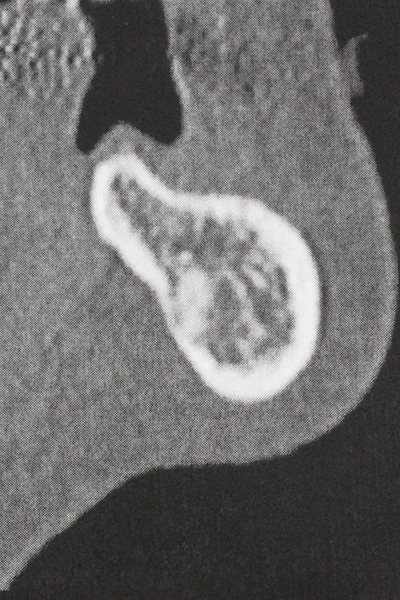

As shown in the past, basically any bone surgery procedure represents a possible indication for piezo surgery. Thus preparation of the mobile segment in distraction osteogenesis (Fig. 23-25) and sandwich osteotomy uses special attachments without endangering the blood supply to the crestal section, which is essential for the success of both techniques (Gonzalez-Garcia, Diniz-Freitas et al. 2008).

Purely orthodontic indications include orthognathic surgery, genioplasty (Fig. 27-30) and orbital decompression in patients with advanced endocrine orbitopathy as a result of Basedow’s disease (Ponto, Zwiener et al. 2014). Piezo devices are also used in maxillofacial surgery and to remove tumours at the base of the skull in various hospitals.